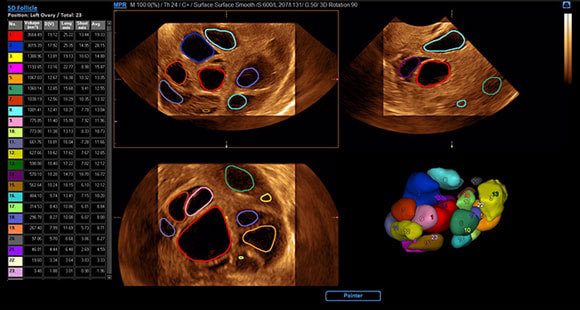

5D Follicle

Foliculul 5D identifică și măsoară mulți foliculi ovarieni pentru evaluarea rapidă a dimensiunii și stării foliculare în timpul examinărilor ginecologice.